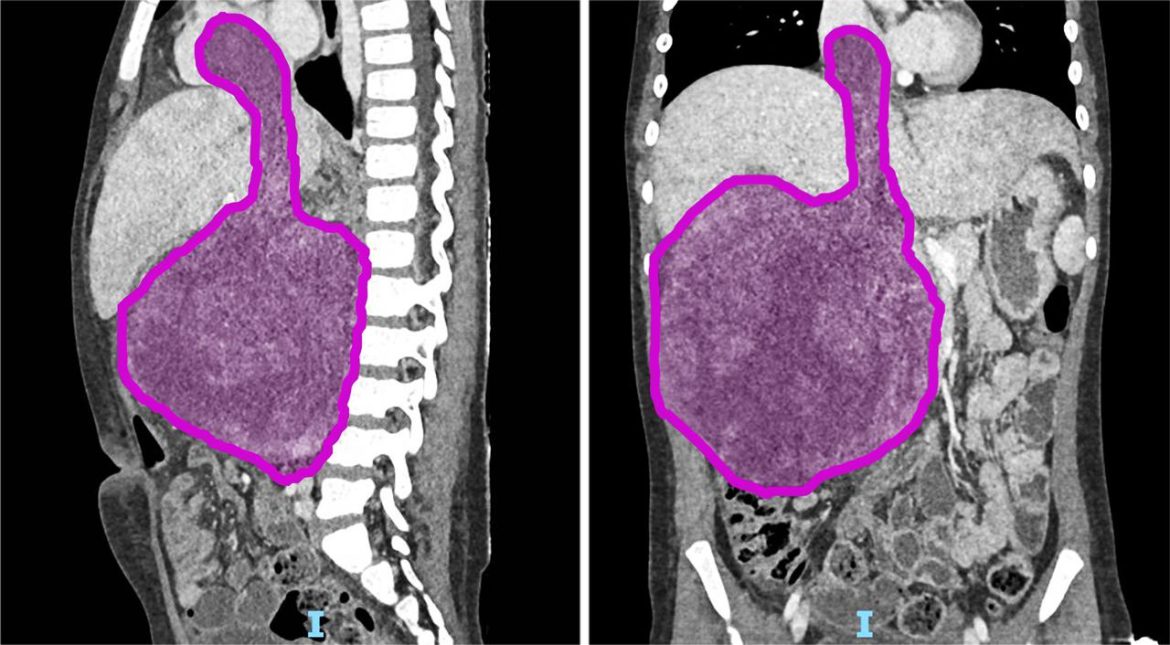

Roma, 20 gen. (Adnkronos Salute) – Sei cicli di chemioterapia, poi nove ore di intervento ma ora il tumore di circa 1,5 chili di cui era affetta Sara (nome di fantasia), a soli otto anni, è stato rimosso. “Un intervento chirurgico complesso e straordinario”, ha spiegato in una nota l’ospedale pediatrico Bambino Gesù di Roma dove è stata operata la bambina. “Questo successo non è solo una vittoria medica, ma anche una grande speranza per tante famiglie che affrontano situazioni simili”, ha affermato Alessandro Crocoli, responsabile dell’Unità di Chirurgia Oncologica.”Sara (nome di fantasia), 8 anni appena compiuti, era affetta da un nefroblastoma al rene destro che si estendeva all’interno della vena renale, della vena cava inferiore fino a raggiungere l’atrio destro del cuore, a causa di una trombosi neoplastica. Questa rara estensione del tumore – ha spiegato l’ospedale – si verifica in appena il 4-10% dei casi di nefroblastoma. Prima dell’intervento Sara è stata sottoposta a sei cicli di chemioterapia, eseguiti dal team di oncologi guidati dal professor Franco Locatelli, per ridurre la massa tumorale e facilitare l’operazione. La fase preparatoria pre-chirurgica si è avvalsa di tecniche all’avanguardia di diagnostica per immagini come l’elaborazione 3D del tumore da asportare realizzata dall’unità di Imaging avanzato cardiotoracovascolare e fetale”. “L’intervento, reso possibile dalla collaborazione tra oncologi, chirurghi, cardiochirurghi, e anestesisti, rappresenta un risultato importante per la medicina pediatrica”, ha reso noto l’ospedale pediatrico Bambino Gesù. L’operazione ha avuto una prima fase in cui l’équipe di chirurgia oncologica, formata dal dottor Alessandro Crocoli e dalla dottoressa Chiara Grimaldi, ha rimosso il rene destro, “il cui volume era dieci volte superiore rispetto alla norma a causa del tumore. Successivamente i cardiochirurghi, guidati dal professor Lorenzo Galletti e con il dottor Gianluca Brancaccio come primo operatore, hanno temporaneamente arrestato il cuore della bambina, mantenendola in vita con la circolazione extracorporea, per rimuovere la parte del tumore che aveva invaso l’atrio destro – prosegue la nota dell’ospedale del Vaticano – Infine, dopo aver riavviato il cuore, i chirurghi hanno completato l’operazione rimuovendo il residuo tumorale dalla vena cava inferiore. In totale, il tumore asportato pesava circa 1,5 kg. La parte anestesiologica del complesso intervento, durato più di 9 ore, è stata gestita dal team della Terapia Intensiva Cardiochirurgica del dottor Luca Di Chiara”.”Questo successo non è solo una vittoria medica, ma anche una grande speranza per tante famiglie che affrontano situazioni simili: rappresenta un traguardo straordinario nella chirurgia oncologica pediatrica. Rimuovere un tumore di queste dimensioni, così invasivo, è stato possibile solo grazie a una pianificazione chirurgica estremamente accurata e alla collaborazione di un’équipe multidisciplinare altamente specializzata – ha detto Alessandro Crocoli, responsabile di Chirurgia Oncologica – La priorità è stata garantire il miglior risultato possibile, con un approccio personalizzato e sicuro”.”L’asportazione della massa tumorale che invadeva il cuore ha richiesto l’arresto cardiaco e l’uso della circolazione extracorporea, procedure complesse che esigono il massimo coordinamento – ha commentato il professor Lorenzo Galletti, responsabile di Cardiochirurgia – Questo intervento dimostra come, unendo competenze avanzate e tecnologia d’avanguardia, possiamo affrontare anche i casi più difficili, restituendo speranza ai nostri giovani pazienti”. Dopo una breve degenza in terapia intensiva, Sara “sta proseguendo la convalescenza in modo positivo e riceve le cure necessarie per un recupero ottimale. La scorsa settimana ha festeggiato il suo ottavo compleanno in reparto con la famiglia e con i medici che si stanno prendendo cura di lei. Il suo percorso di cura continuerà con sedute di radioterapia addominale e ulteriori cicli di chemioterapia”, conclude l’ospedale.Il nefroblastoma, noto anche come tumore di Wilms, “è una neoplasia rara che colpisce prevalentemente i bambini tra 1 e 5 anni, con un picco tra i 2 e i 3 anni. Rappresenta circa il 90% dei tumori renali pediatrici, anche se i tumori al rene costituiscono meno del 5% delle neoplasie in età pediatrica – ricorda l’ospedale – In Italia, la sua incidenza è di circa 8 casi ogni milione di bambini. I reni si formano durante lo sviluppo embrionale a partire da alcune particolari cellule staminali dette progenitrici. In alcuni casi, queste cellule persistono nei reni dopo la nascita e, a causa di mutazioni genetiche, possono proliferare in modo incontrollato, portando alla formazione del nefroblastoma”.